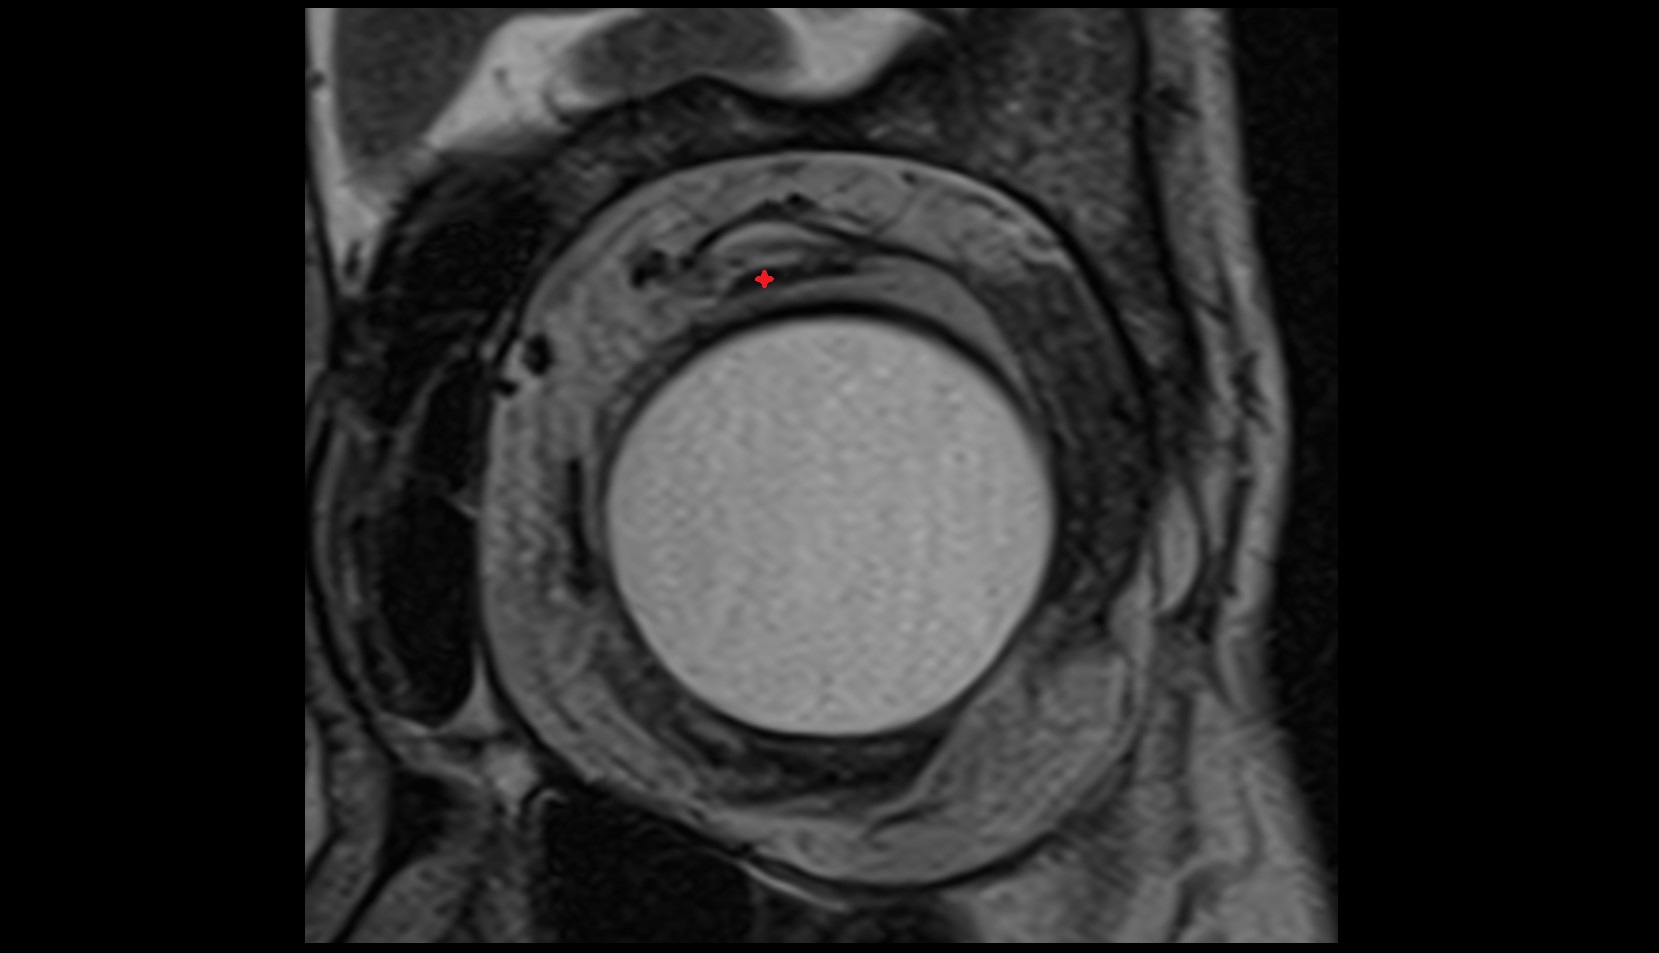

- Peripheral zone of prostate

- Anterior Fibromuscular Stroma of prostate

- Central zone of prostate

- Transitional zone of prostate